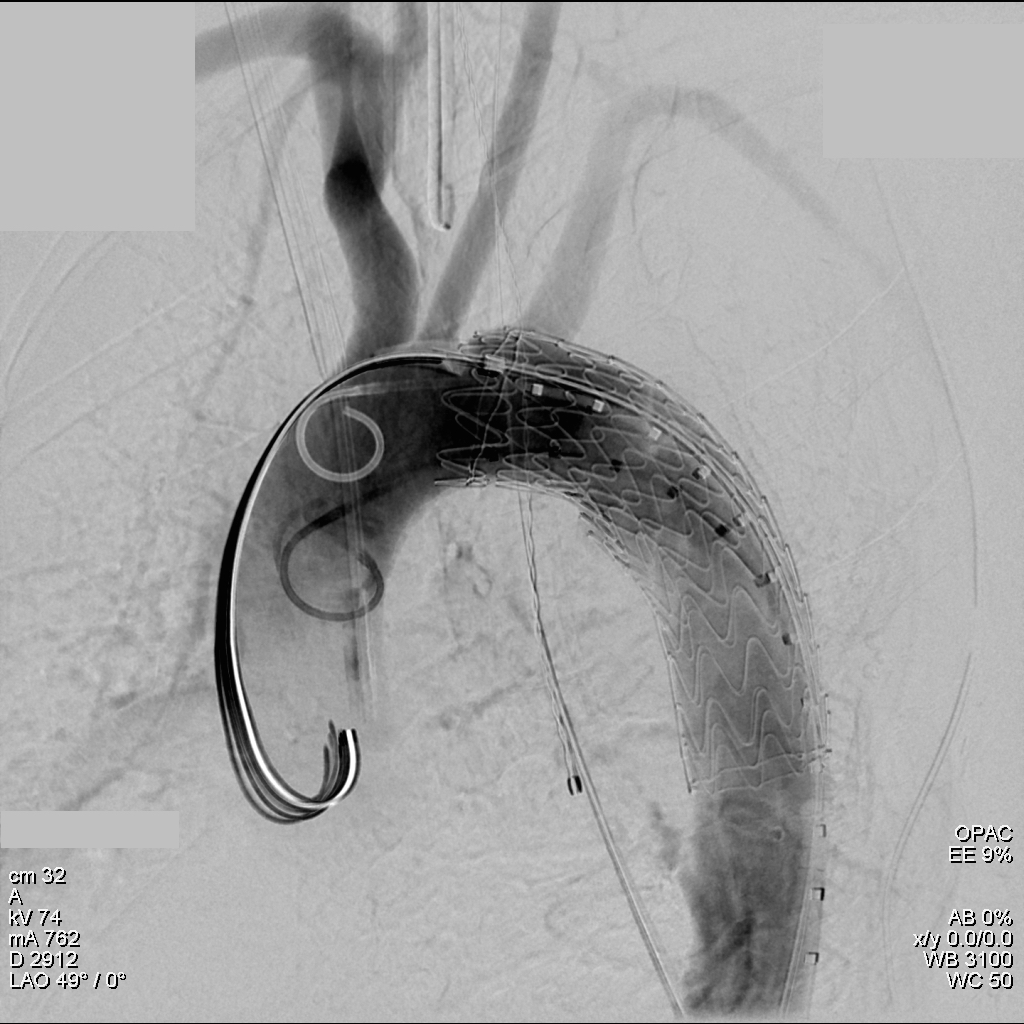

The plaque is extracted and re-establishes patency of the EIA.

The plaque end point is typically treated with a stent -in this case, the common iliac plaque was also treated.

What is nice about this approach is that this artery has been restored to nearly its original condition. I have taken biopsies of the artery several months after the procedure in the process of using the artery as inflow for a cross femoral bypass, and the artery clamped and sewed like a normal artery and the pathology returned normal artery.

This has several advantages over conduit creation which can be a morbid and high risk procedure in patients who require minimally invasive approach. A graft is avoided. The artery is over 8mm in diameter where with stenting up to 8mm with an occlusive plaque, the danger of rupture is present, and often ballooning is restricted to 6mm-7mm. This is insufficient for many TEVAR grafts and TAVR valves.